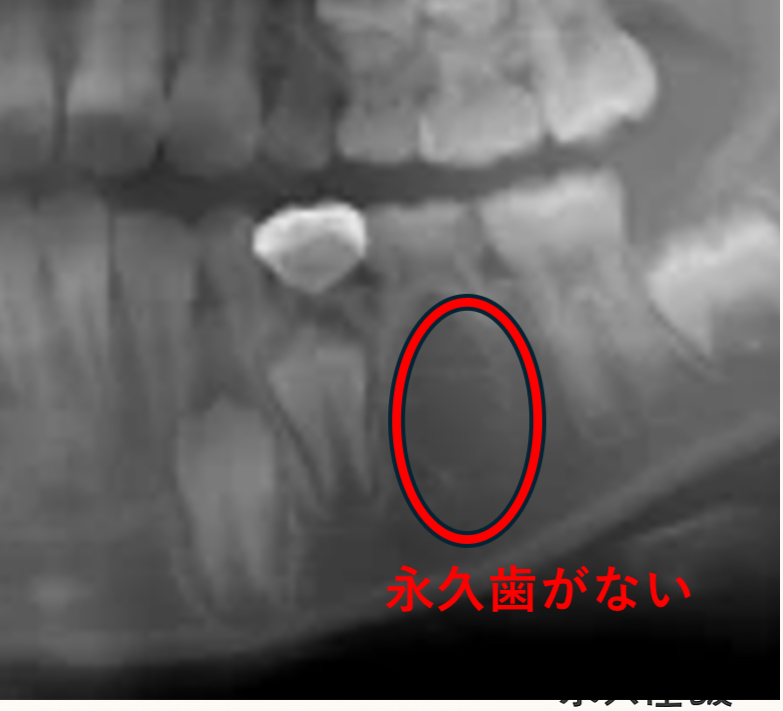

「歯の本数が足りない」永久歯の先天欠如について

永久歯の「先天欠如(せんてんけつじょ)」とは、生まれつき一部の永久歯の“種”が存在しない状態をいいます。

乳歯はすべて生えてくることが多いため、子どものうちは気づかれないことがほとんどです。

多くの場合、虫歯などを確認するために撮ったレントゲンで、結果的に先天欠如が見つかります。

特別な検査ではなく、日常的なチェックの中で偶然分かるケースが多いのです。